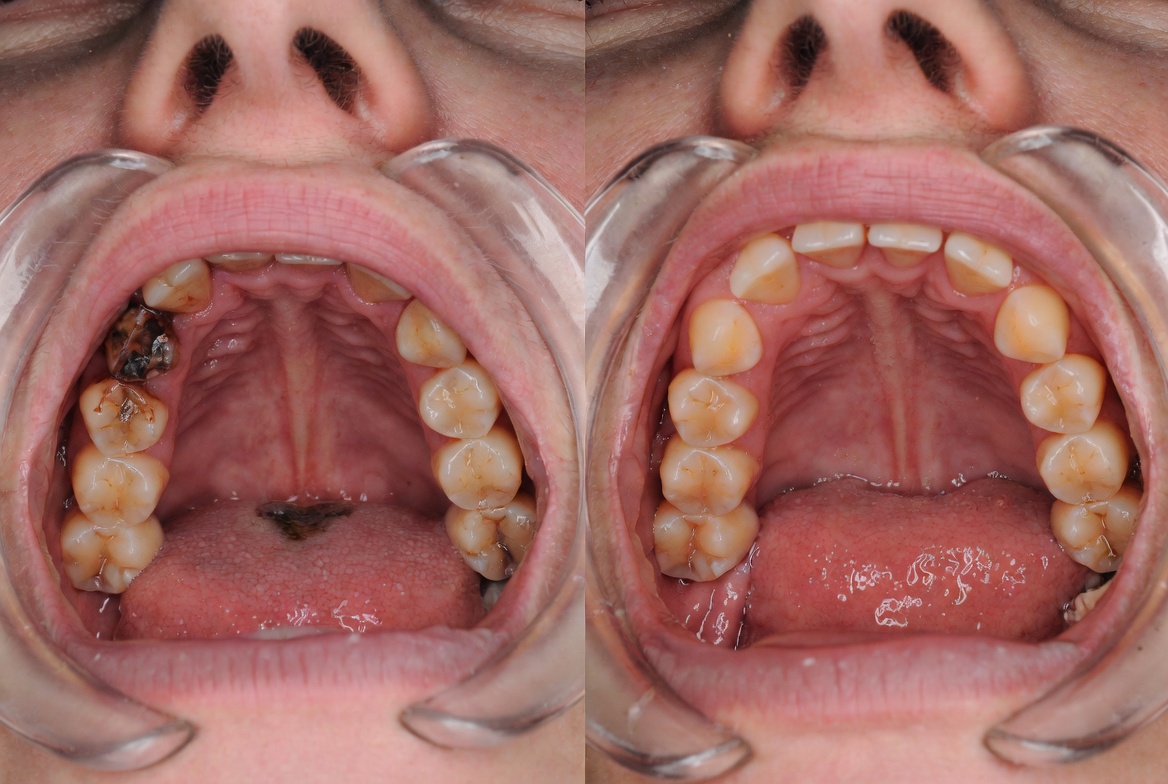

Severely decayed tooth with no remaining restorable structure

Cracked tooth with fracture extending below the gum line

Tooth with advanced bone loss from gum disease

Infected tooth with spreading abscess requiring immediate removal